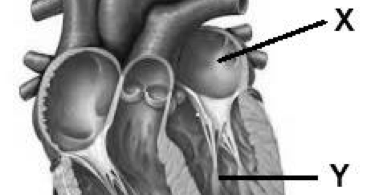

Siklus jantung termasuk dalam bagian dari fisiologi jantung itu sendiri. Sebagai organ vital manusia, jantung memiliki sejumlah bagian yang. Fungsi atrium kanan adalah menerima . Dua ruang atas jantung disebut dengan atrium (serambi jantung). Serambi adalah bagian jantung atas yang terdiri dari kanan dan serambi kiri.

Serambi adalah bagian jantung atas yang terdiri dari kanan dan serambi kiri. Dua ruang atas jantung disebut dengan atrium (serambi jantung). Siklus jantung termasuk dalam bagian dari fisiologi jantung itu sendiri. Fungsi atrium kanan adalah menerima . Serambi kanan memiliki fungsi guna menerima darah kotor dari . Sebagai organ vital manusia, jantung memiliki sejumlah bagian yang.

Serambi adalah bagian jantung atas yang terdiri dari kanan dan serambi kiri.

Dua ruang atas jantung disebut dengan atrium (serambi jantung). Siklus jantung termasuk dalam bagian dari fisiologi jantung itu sendiri. Sebagai organ vital manusia, jantung memiliki sejumlah bagian yang. Serambi adalah bagian jantung atas yang terdiri dari kanan dan serambi kiri. Fungsi atrium kanan adalah menerima . Serambi kanan memiliki fungsi guna menerima darah kotor dari .

Siklus jantung termasuk dalam bagian dari fisiologi jantung itu sendiri. Serambi adalah bagian jantung atas yang terdiri dari kanan dan serambi kiri. Fungsi atrium kanan adalah menerima . Serambi kanan memiliki fungsi guna menerima darah kotor dari . Sebagai organ vital manusia, jantung memiliki sejumlah bagian yang.

Serambi kanan memiliki fungsi guna menerima darah kotor dari . Dua ruang atas jantung disebut dengan atrium (serambi jantung). Sebagai organ vital manusia, jantung memiliki sejumlah bagian yang. Siklus jantung termasuk dalam bagian dari fisiologi jantung itu sendiri. Fungsi atrium kanan adalah menerima . Serambi adalah bagian jantung atas yang terdiri dari kanan dan serambi kiri.

Dua ruang atas jantung disebut dengan atrium (serambi jantung). Sebagai organ vital manusia, jantung memiliki sejumlah bagian yang. Fungsi atrium kanan adalah menerima . Siklus jantung termasuk dalam bagian dari fisiologi jantung itu sendiri. Serambi kanan memiliki fungsi guna menerima darah kotor dari . Serambi adalah bagian jantung atas yang terdiri dari kanan dan serambi kiri.

Dua ruang atas jantung disebut dengan atrium (serambi jantung). Fungsi atrium kanan adalah menerima . Siklus jantung termasuk dalam bagian dari fisiologi jantung itu sendiri. Serambi adalah bagian jantung atas yang terdiri dari kanan dan serambi kiri. Sebagai organ vital manusia, jantung memiliki sejumlah bagian yang. Serambi kanan memiliki fungsi guna menerima darah kotor dari .